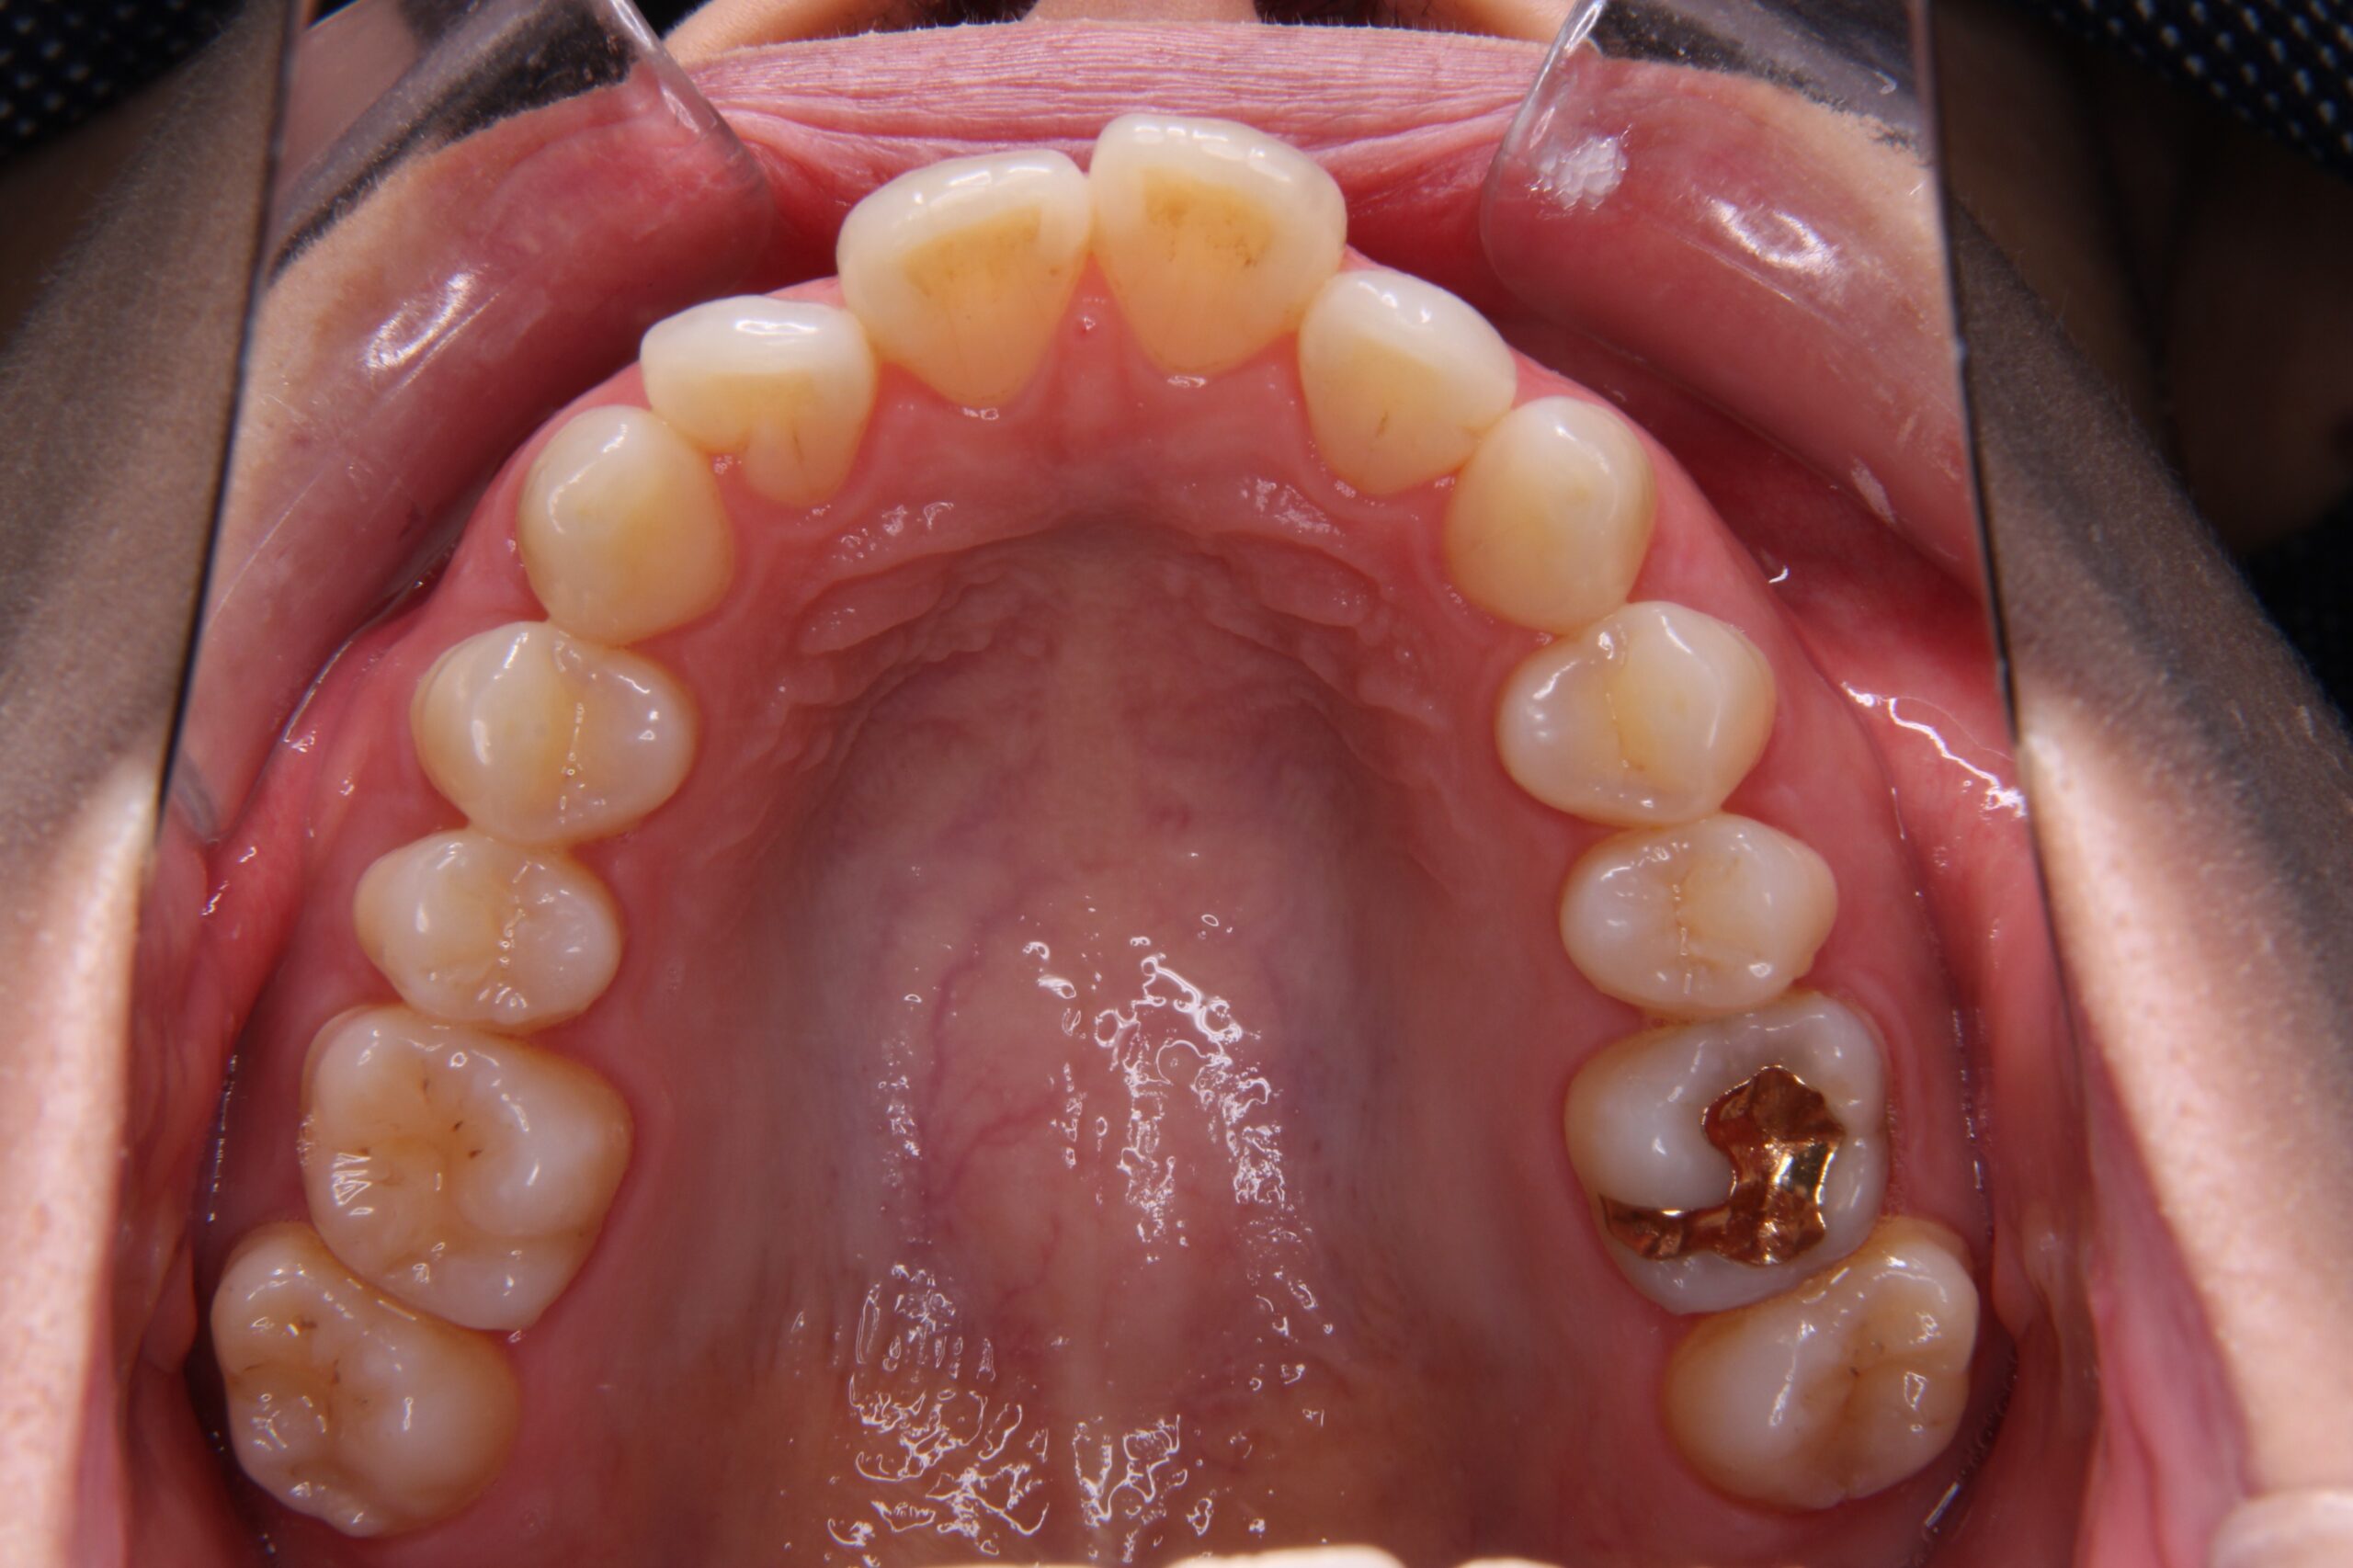

私自身は、特に、「前突」と「下顎の叢生」「過蓋咬合」が気になっていました。

矯正治療前の歯列がこちらです↓↓↓